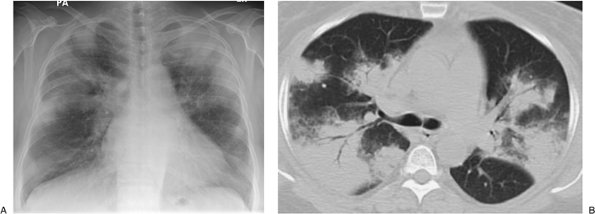

FIGURE 12-1. Usual interstitial pneumonitis. A: Posteroanterior (PA) chest radiograph of a 72-year-old woman with scleroderma shows low lung volumes and bilateral reticular interstitial lung disease. B: CT shows that the reticular opacities have a subpleural, peripheral distribution (arrows).

FIGURE 12-2. Eosinophilic pneumonia. A: PA chest radiograph of a 21-year-old woman shows bilateral airspace opacities that extend to the lung periphery. B: CT better shows the peripheral distribution of disease. Note prominent air bronchograms.